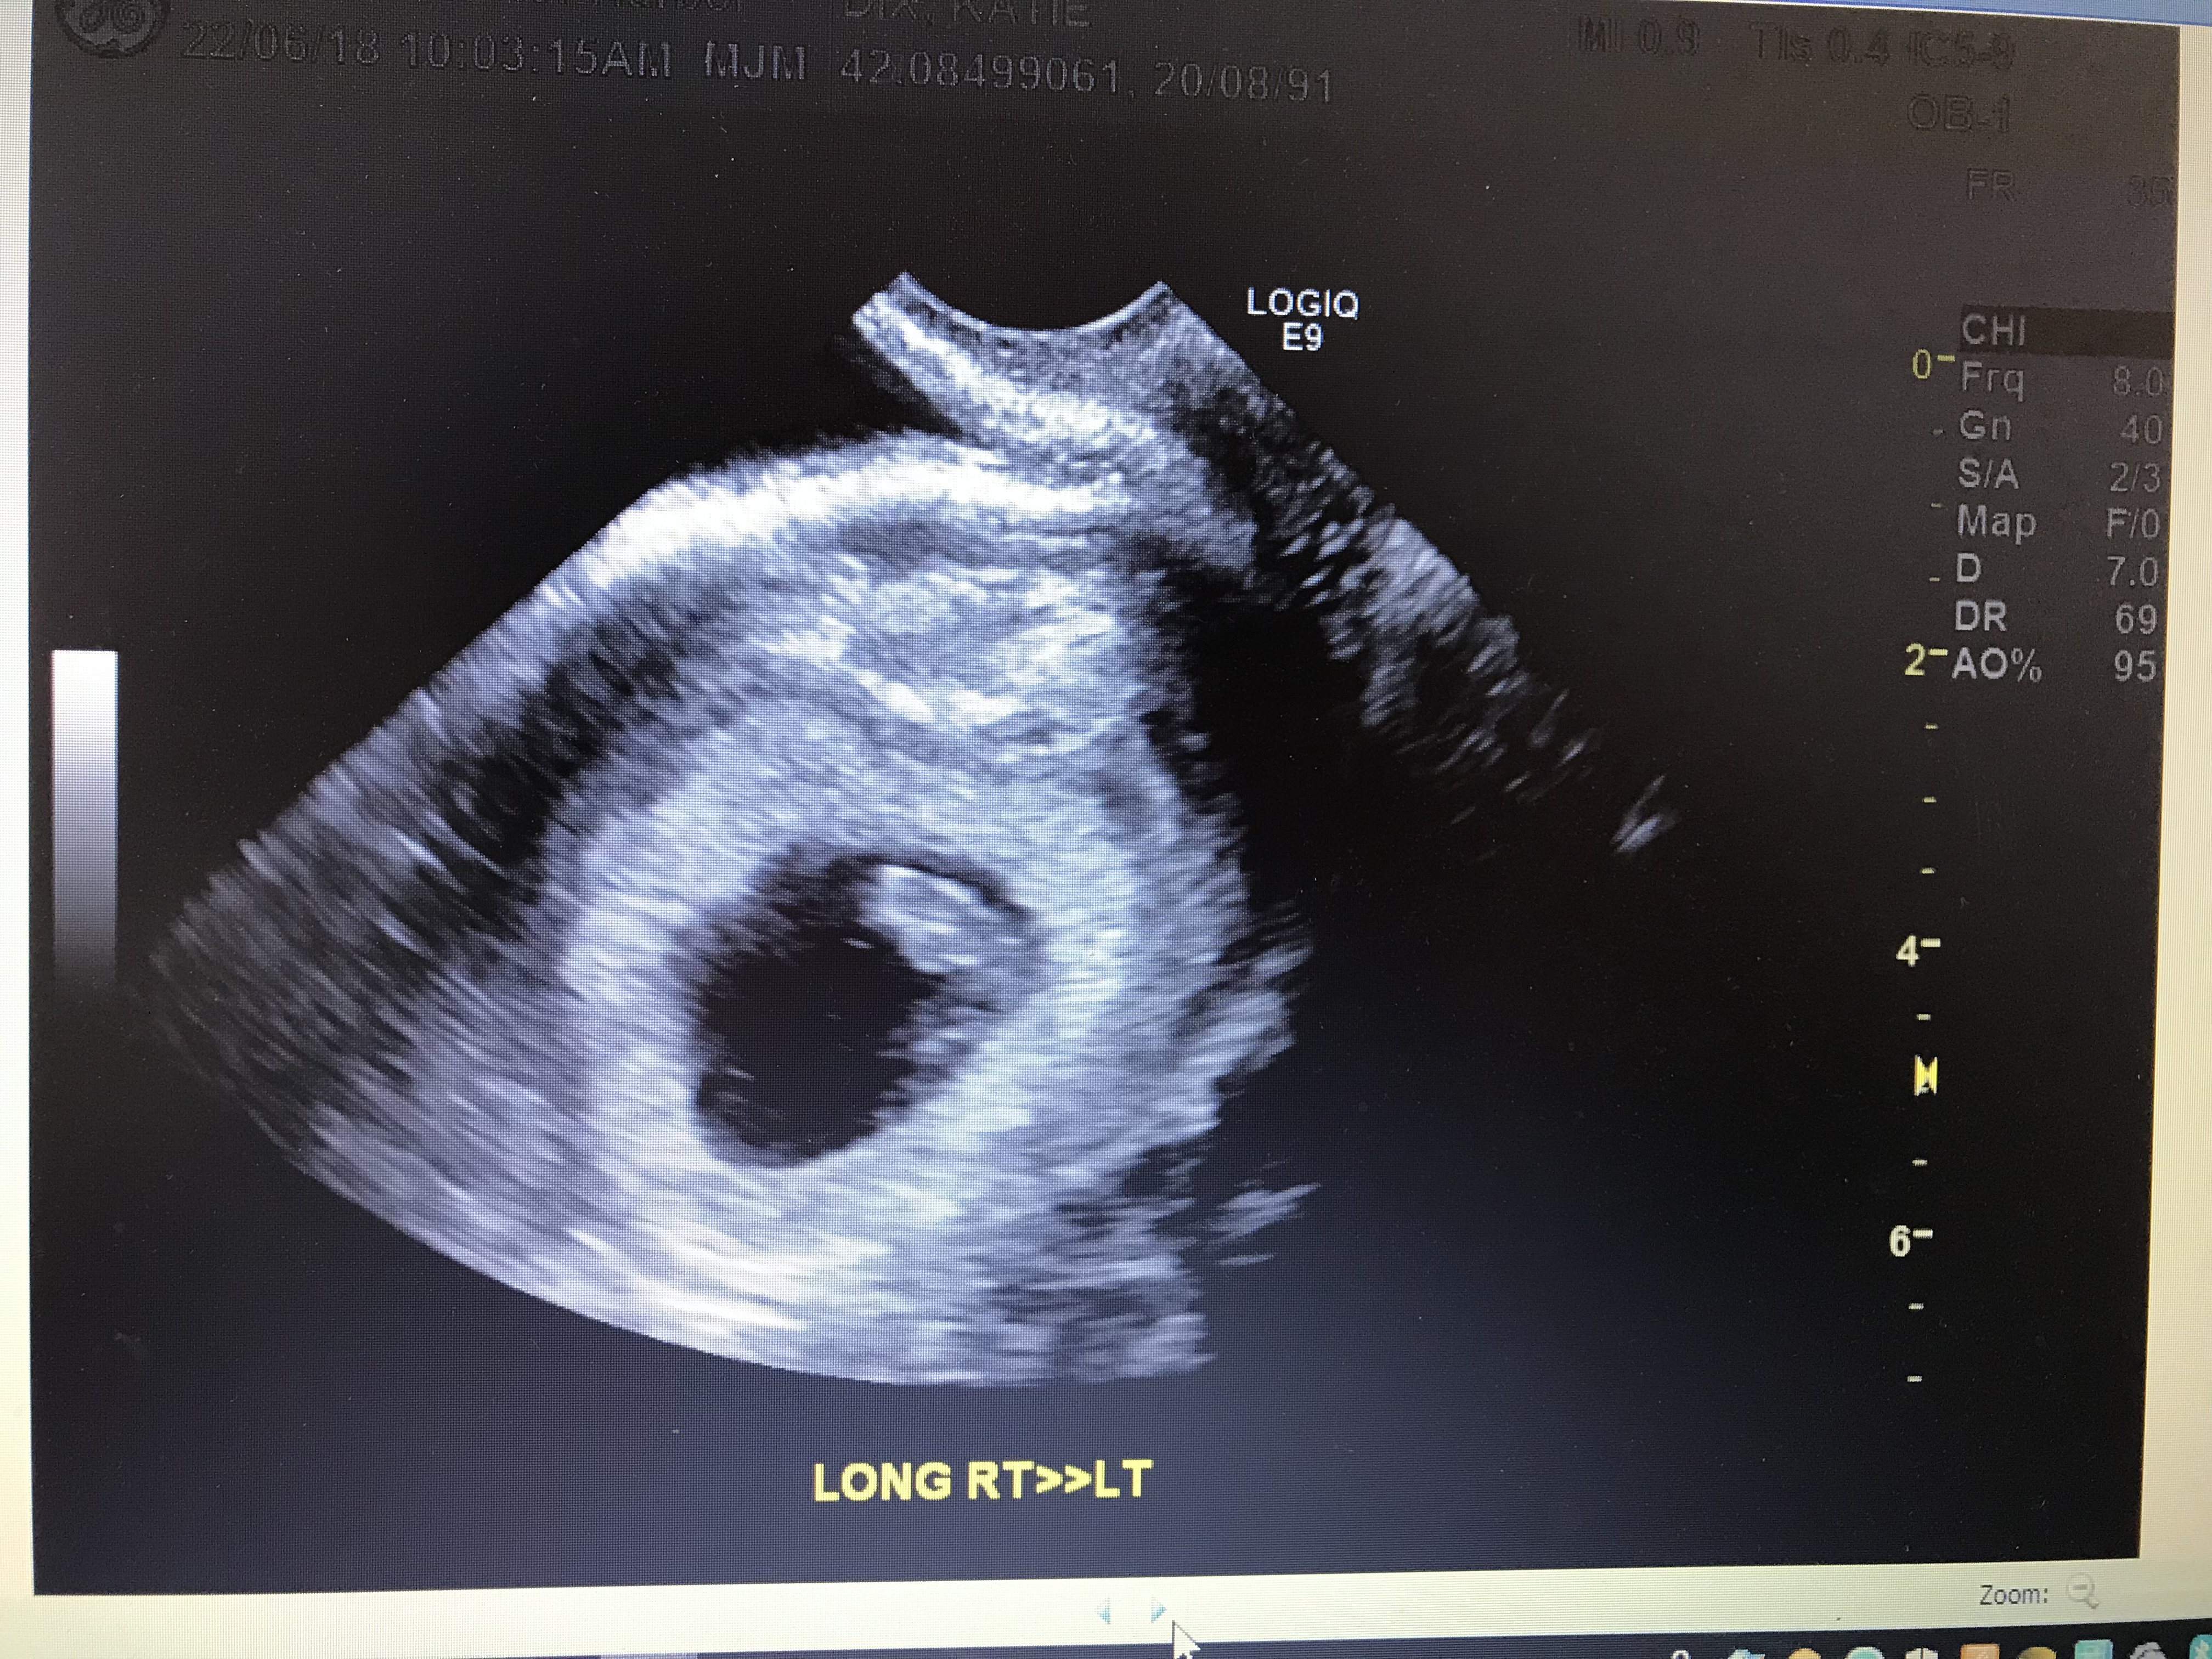

… well it was a scan that shook our world. As the sonographer moved the ultrasound machine over my tummy she struggled to see anything. I then was asked if she could do an internal exam instead – we agreed. When she did this she got a clearer image but from what she could see if was simply just a yolk sack and had me measuring about 5 weeks. The sonographer explained that all she could see was the sack, so we either had our dates wrong or it was a missed miscarriage – I crumbled. It was such a sickening feeling to think that we had conceived but it had failed to form and that I would have to go through some sort of procedure to remove it from my body. However the sonographer was so wonderful, she said for us to take all the time we needed (instead of kicking us straight back out of the room), and that it could just be our dates being wrong and to not fret yet. My obstetrician also called me the following day to check-in with me and comfort me – our obstetrician was honestly the best, she knows her patients right from the get go and knew I would be upset, struggling and fretting over the unknown. The next two weeks were the absolute hardest, as we had to wait to then have another scan to check. My blood tests had all come back as good, and my hCG levels were good but not overly high. By the time the second scan came around I had convinced myself that I had just mucked up my dates – and this was true. It was such a wave of relief to see our little bean inside – safe and a heart beat. I honestly could not imagine the pain others have gone through at the lose of a baby, the mere thought of this possibility had me broken. So to all you ladies who have suffered, you are amazingly strong and I take my hat off to you, for being able to grow from it and keep on battling to get your precious bundle of joy.